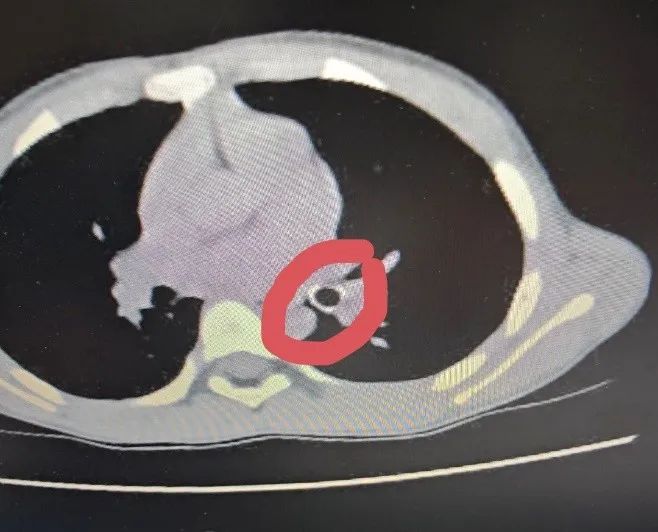

Khi nhập viện, em Đ. tỉnh táo nhưng ho nhiều, khò khè, thở nhanh, thông khí phổi giảm. Qua thăm khám và chẩn đoán hình ảnh, các bác sĩ xác định trẻ bị hóc dị vật đường hô hấp. Dị vật nằm sâu trong phế quản, gây cản trở thông khí. Sau hội chẩn, bệnh nhi được chỉ định nội soi phế quản cấp cứu để lấy dị vật. Thủ thuật được thực hiện an toàn, dị vật là đầu ngòi bút nhựa được lấy ra hoàn toàn. Sau can thiệp, tình trạng hô hấp của trẻ cải thiện rõ rệt và tiếp tục được theo dõi, điều trị tại bệnh viện.